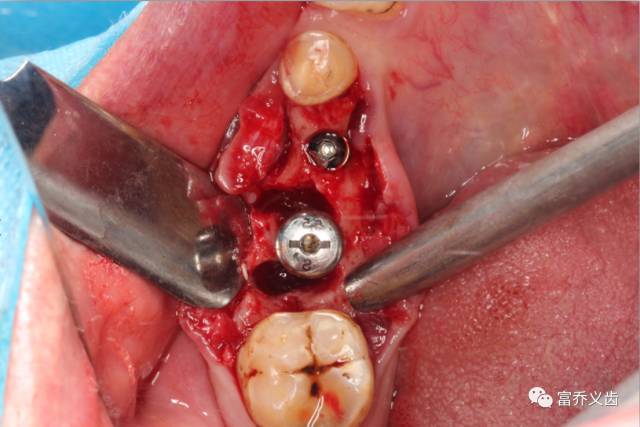

种植术中46远中牙根未拔除先备洞

拔除46牙根

备洞完成,拔除牙根后

植入植体,旋入覆盖螺丝与愈合基台